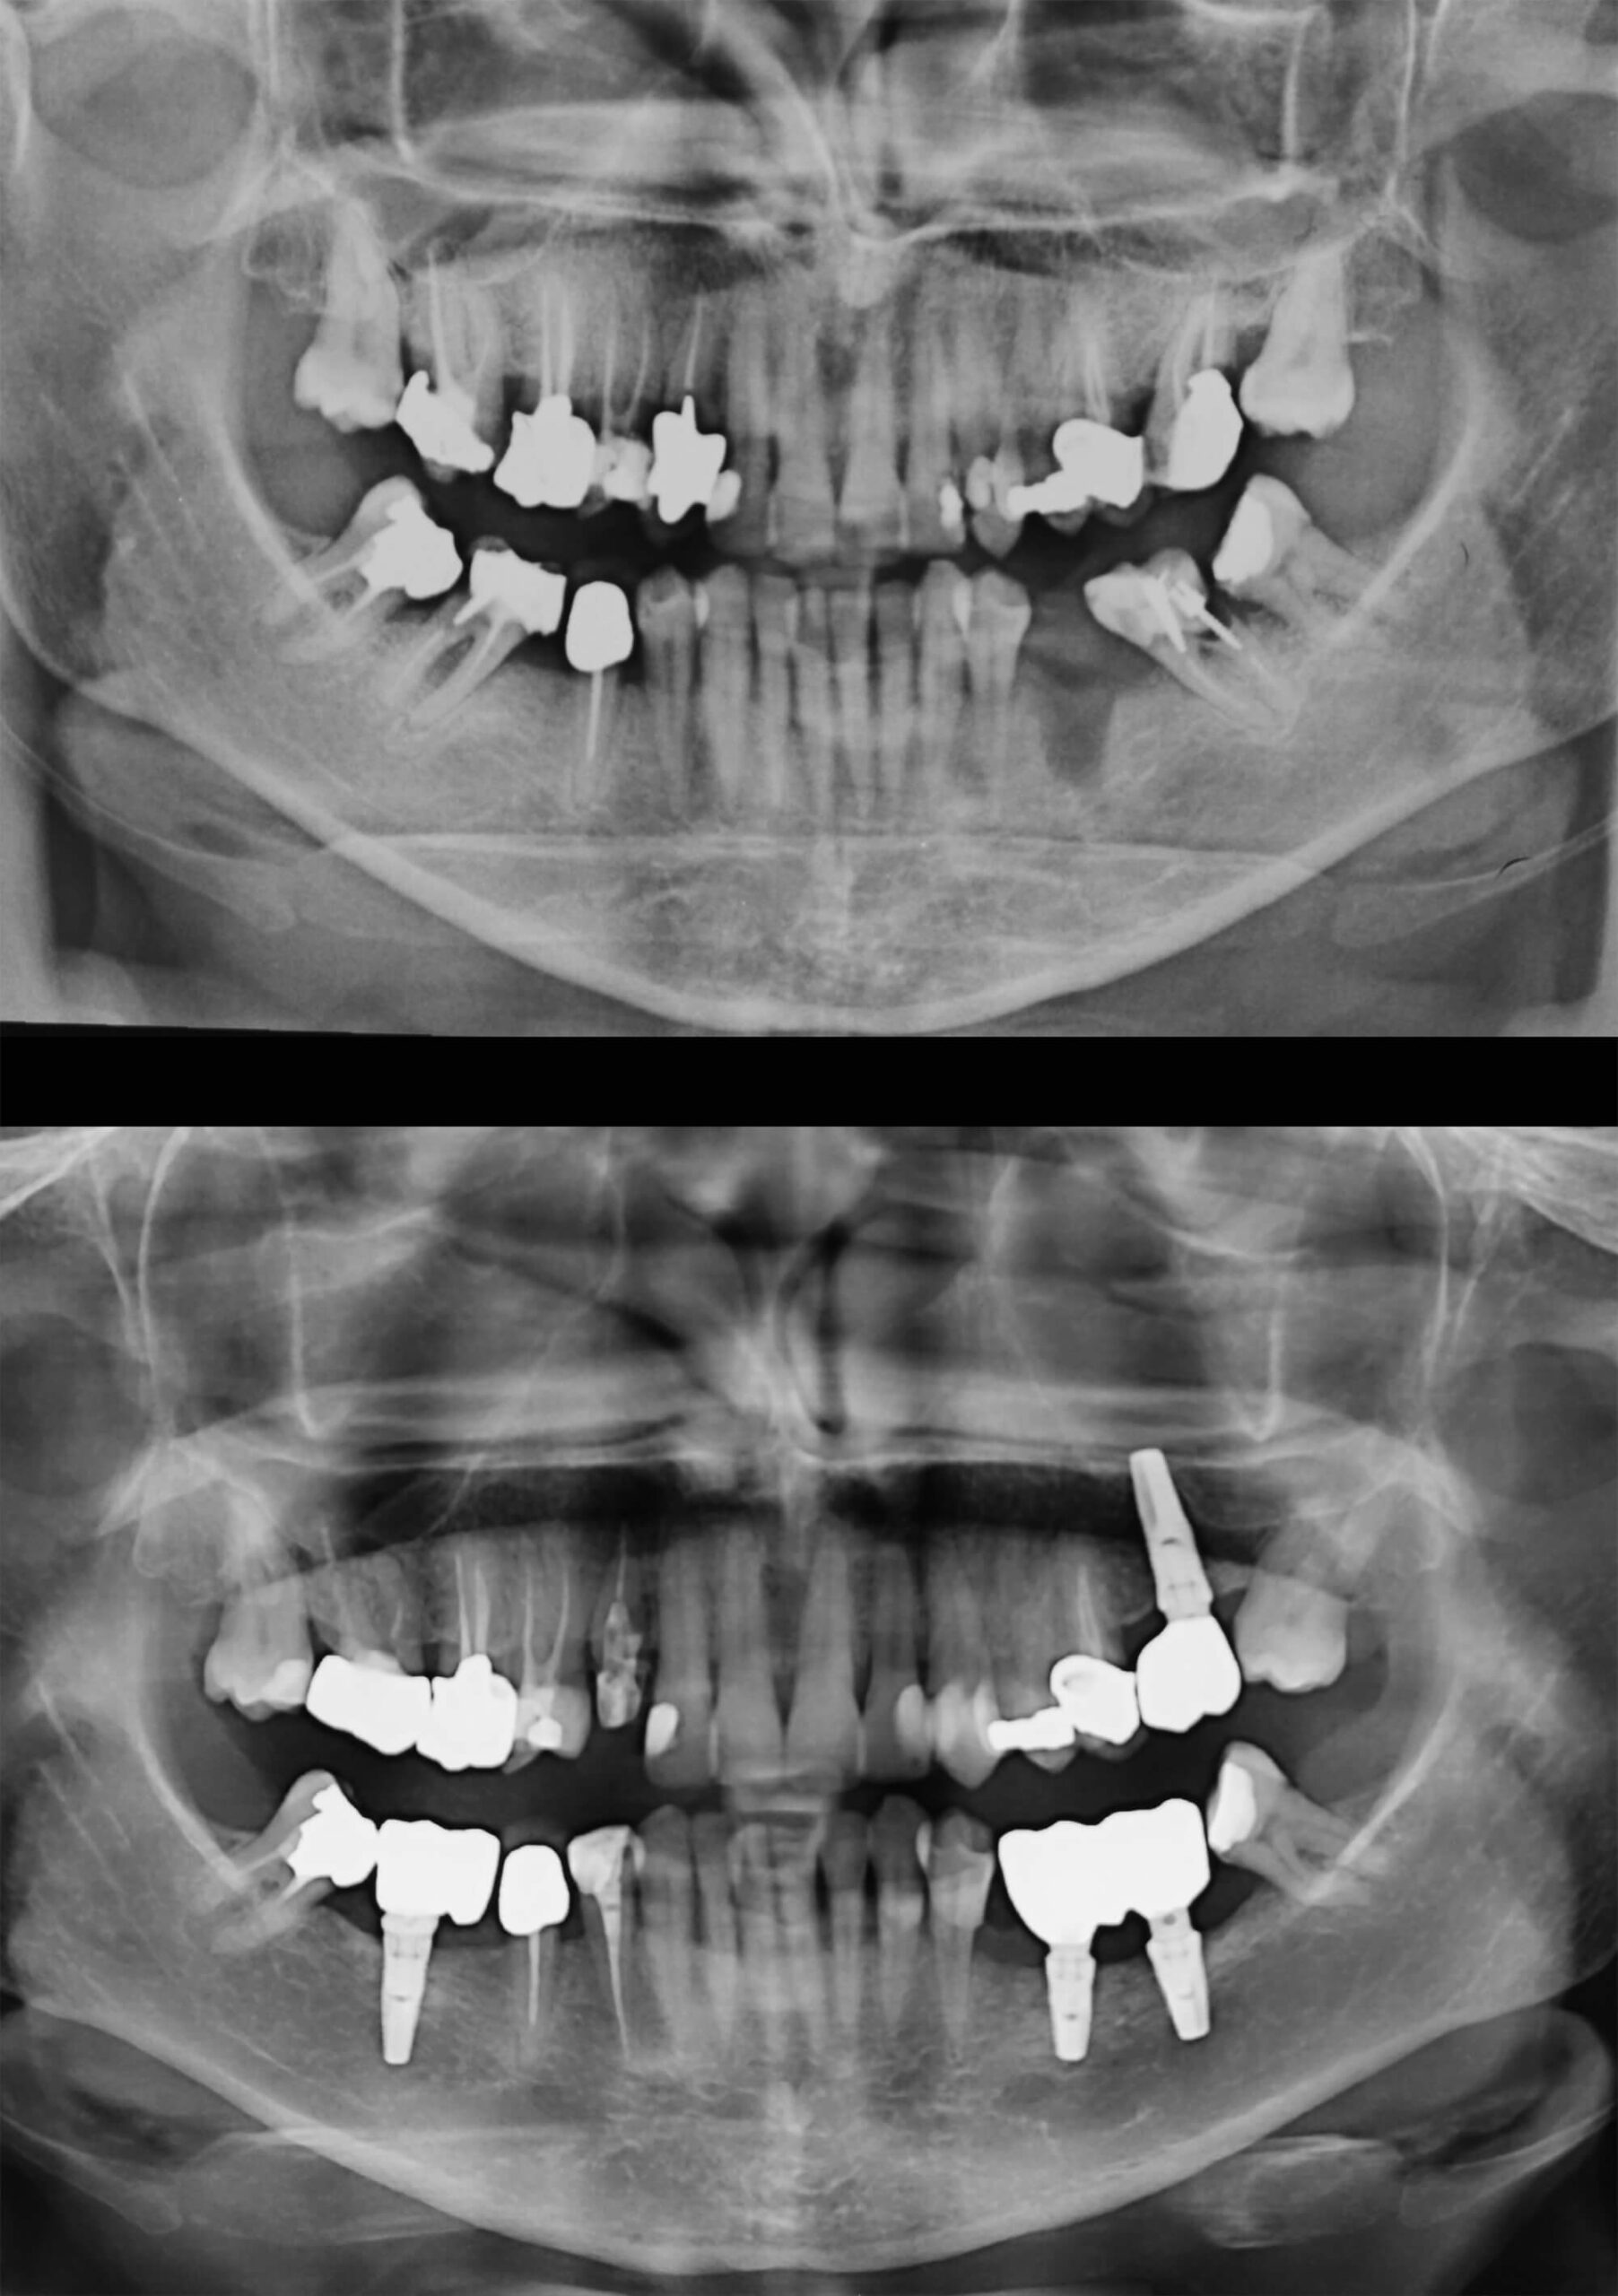

Trattamento Riabilitativo complesso con eliminazione di tutti gli elementi dentari con processi infettivi, Trattamento di Rigenerazione Ossea e Riabilitazione Implanto Protesica finale